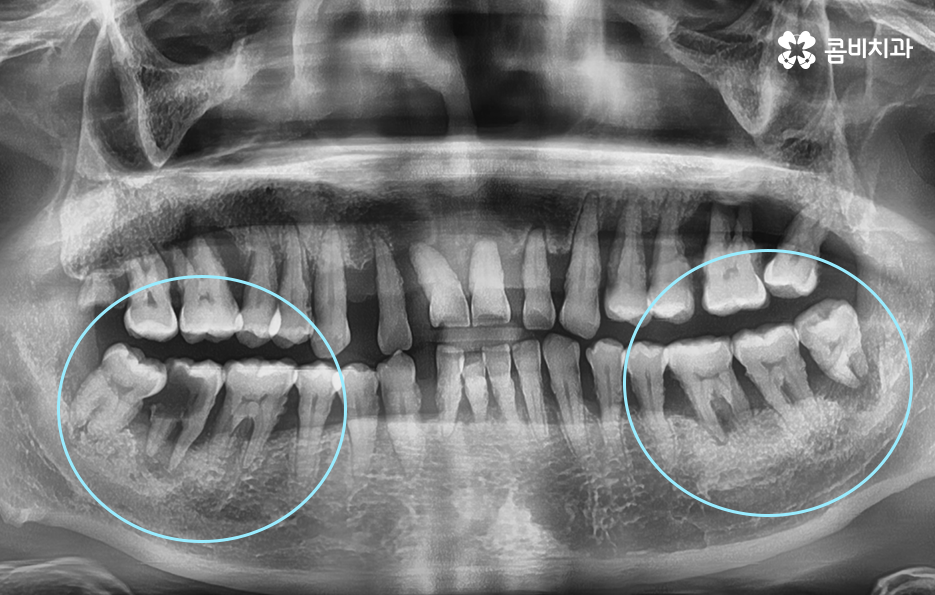

치주염으로 인해 치아를 잃게 되신 분들은 잘 아시겠지만 잇몸이 퇴축되어 있고 잇몸 뼈가 부족하여 임플란트 치료 과정 상에 뼈이식이 필요한 경우가 많고 치아를 한꺼번에 여러 치아를 잃게 되어 임플란트를 여러 개 심어야 하는 경우도 많을 거예요